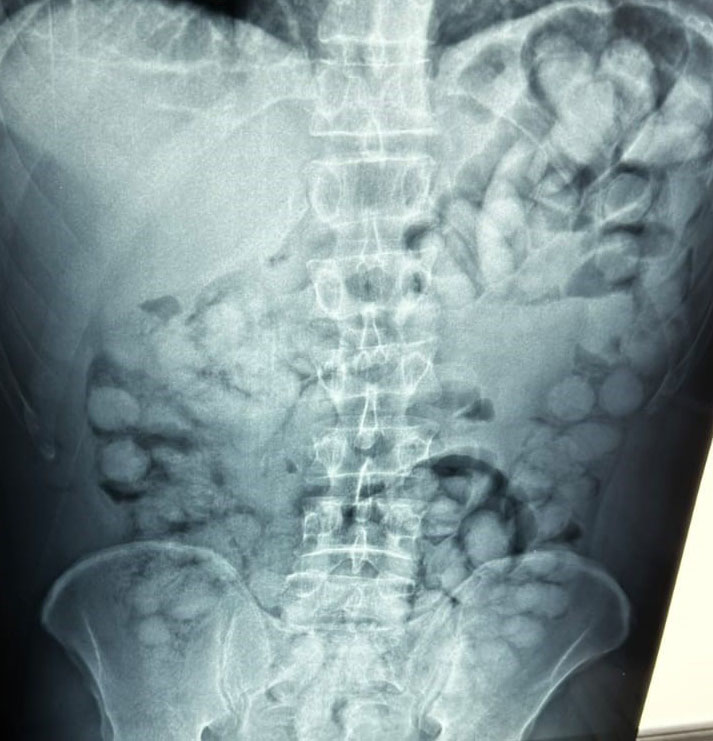

Ο άνδρας, που ταξίδευε από Βραζιλία μέσω Γαλλίας, είχε καταπιεί 100 συσκευασίες κοκαΐνης. Η κάθε συσκευασία ήταν 10 γραμμαρίων και καθαρότητας 90%.